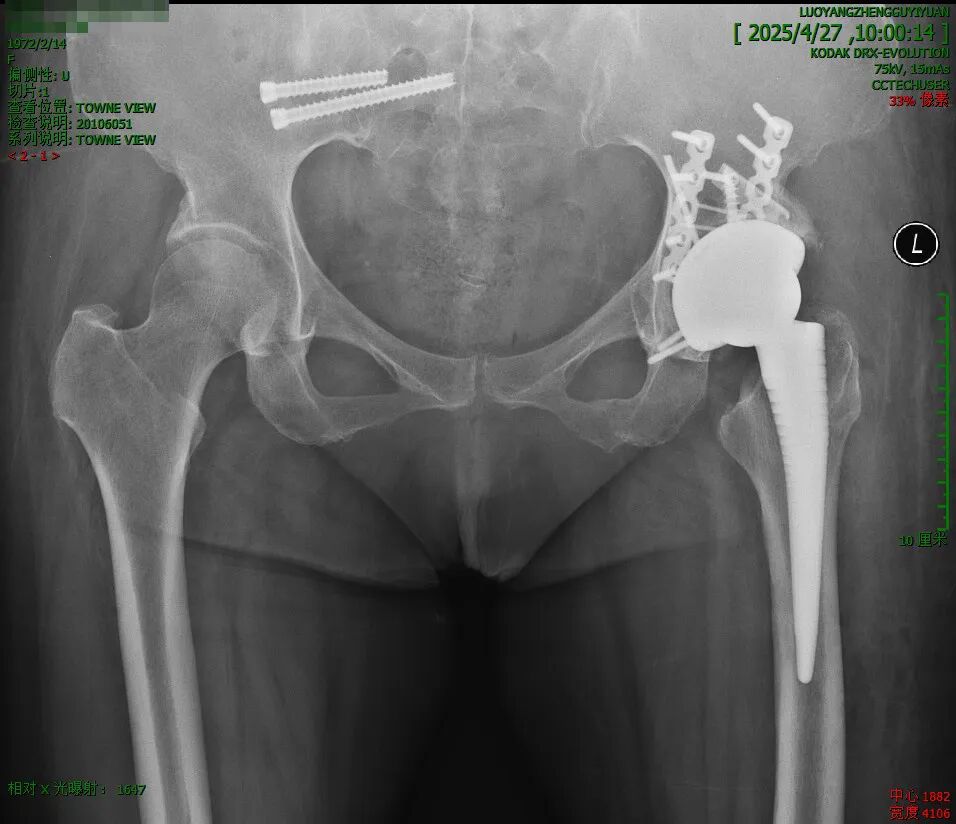

W女士,13年前因髋臼骨折行内固定手术,近2年来左髋部间断疼痛并活动受限、跛行,拟行人工髋关节置换术。

密密麻麻的钉子: